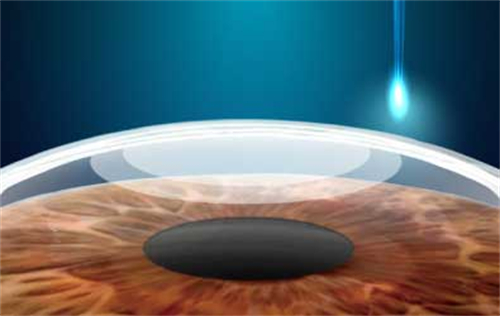

视网膜脱落的治疗方法有多种。对于尚未发生脱离的视网膜裂孔,可采用激光治疗,利用激光封闭裂孔,防止视网膜脱落。传统的巩膜环扎术和巩膜外加压术,适用于单纯的早期视网膜脱离。